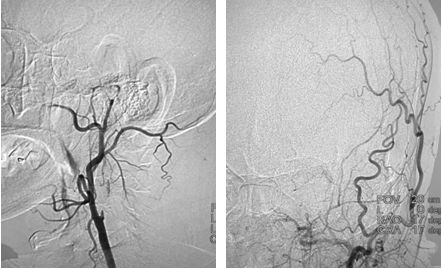

DSA结果提示:左侧颈内动脉次全闭塞,远端未见显影,左侧大脑中动脉闭塞,前交通动脉开放,左侧椎动脉起始部重度狭窄(图3-5)。

图3

图4

图5